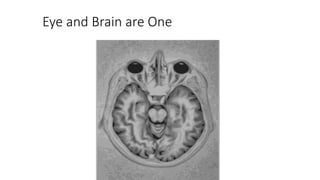

Eye and Brain are One

Brain Plasticity

• Vision happens in 40 different parts of the brain.

• With use, visual connections and associations

form.

• Using these brain areas is important: early and

often.